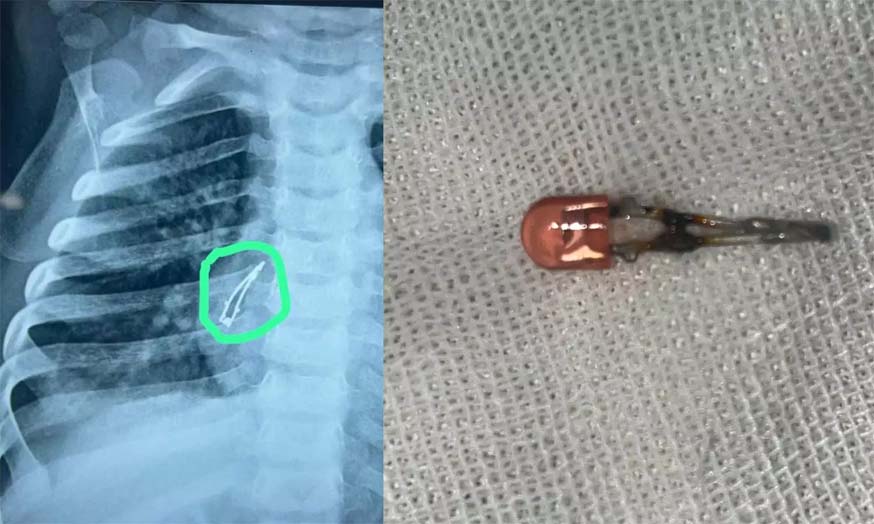

രണ്ടാഴ്ചയോളം ചുമ; ഒന്പത് മാസം പ്രായമുള്ള കുഞ്ഞിന്റെ ശ്വാസനാളത്തില്നിന്ന് പുറത്തെടുത്തത് എല്ഇഡി ബള്ബ്

ഗാന്ധിനഗര്: ഒന്പത് മാസം പ്രായമുള്ള കുഞ്ഞ് അബദ്ധത്തില് വിഴുങ്ങിയ എല്ഇഡി ബള്ബ് ഓപ്പറേഷനിലൂടെ പുറത്തെടുത്തു. ഗുജറാത്തിലെ അഹമ്മദാബാദിലായിരുന്നു സംഭവം. രണ്ടാഴ്ചത്തോളം ചുമ മാറാത്തത് കൊണ്ടാണ് മുഹമ്മദ് എന്ന് പേരുള്ള കുട്ടിയെ അഹമ്മദാബാദ് സിവില് ആശുപത്രിയില് പ്രവേശിപ്പിച്ചത്.

ജുനഗഡിലെ ഒരു ശിശുരോഗ വിദഗ്ദ്ധനെയാണ് കുട്ടിയുടെ മാതാപിതാക്കള് ആദ്യം സമീപിച്ചത്. അദ്ദേഹം തുടര് ചികിത്സയ്ക്കായി ആശുപത്രിയിലേക്ക് റഫര് ചെയ്യുകയായിരുന്നു. അവിടെ നടത്തിയ പരിശോധനയിലാണ് കുഞ്ഞിന്റെ ശ്വാസനാളത്തില് എല്ഇഡി ബള്ബ് കണ്ടെത്തിയത്. പിന്നീട് ബ്രോങ്കോസ്കോപ്പി നടത്തി കുഞ്ഞിന്റെ ശ്വാസനാളത്തില് നിന്ന് ബള്ബ് നീക്കം ചെയ്തു.

കുട്ടി ആരോഗ്യവാനായിരിക്കുന്നു എന്നും ഉടന് ആശുപത്രി വിടുമെന്നും അധികൃതര് അറിയിച്ചു. കുട്ടി കളിപ്പാട്ടം ഉപയോഗിച്ച് കളിക്കുമ്പോഴാണ് സംഭവം നടന്നതെന്ന് മാതാപിതാക്കള് പറഞ്ഞു. എല്ഇഡി ബള്ബ് വേര്പെട്ട് അബദ്ധത്തില് ഇത് വിഴുങ്ങുകയായിരുന്നു. ഇത് ചുമയ്ക്കും അസ്വസ്ഥതകള്ക്കും കാരണമാവുകയായിരുന്നു.